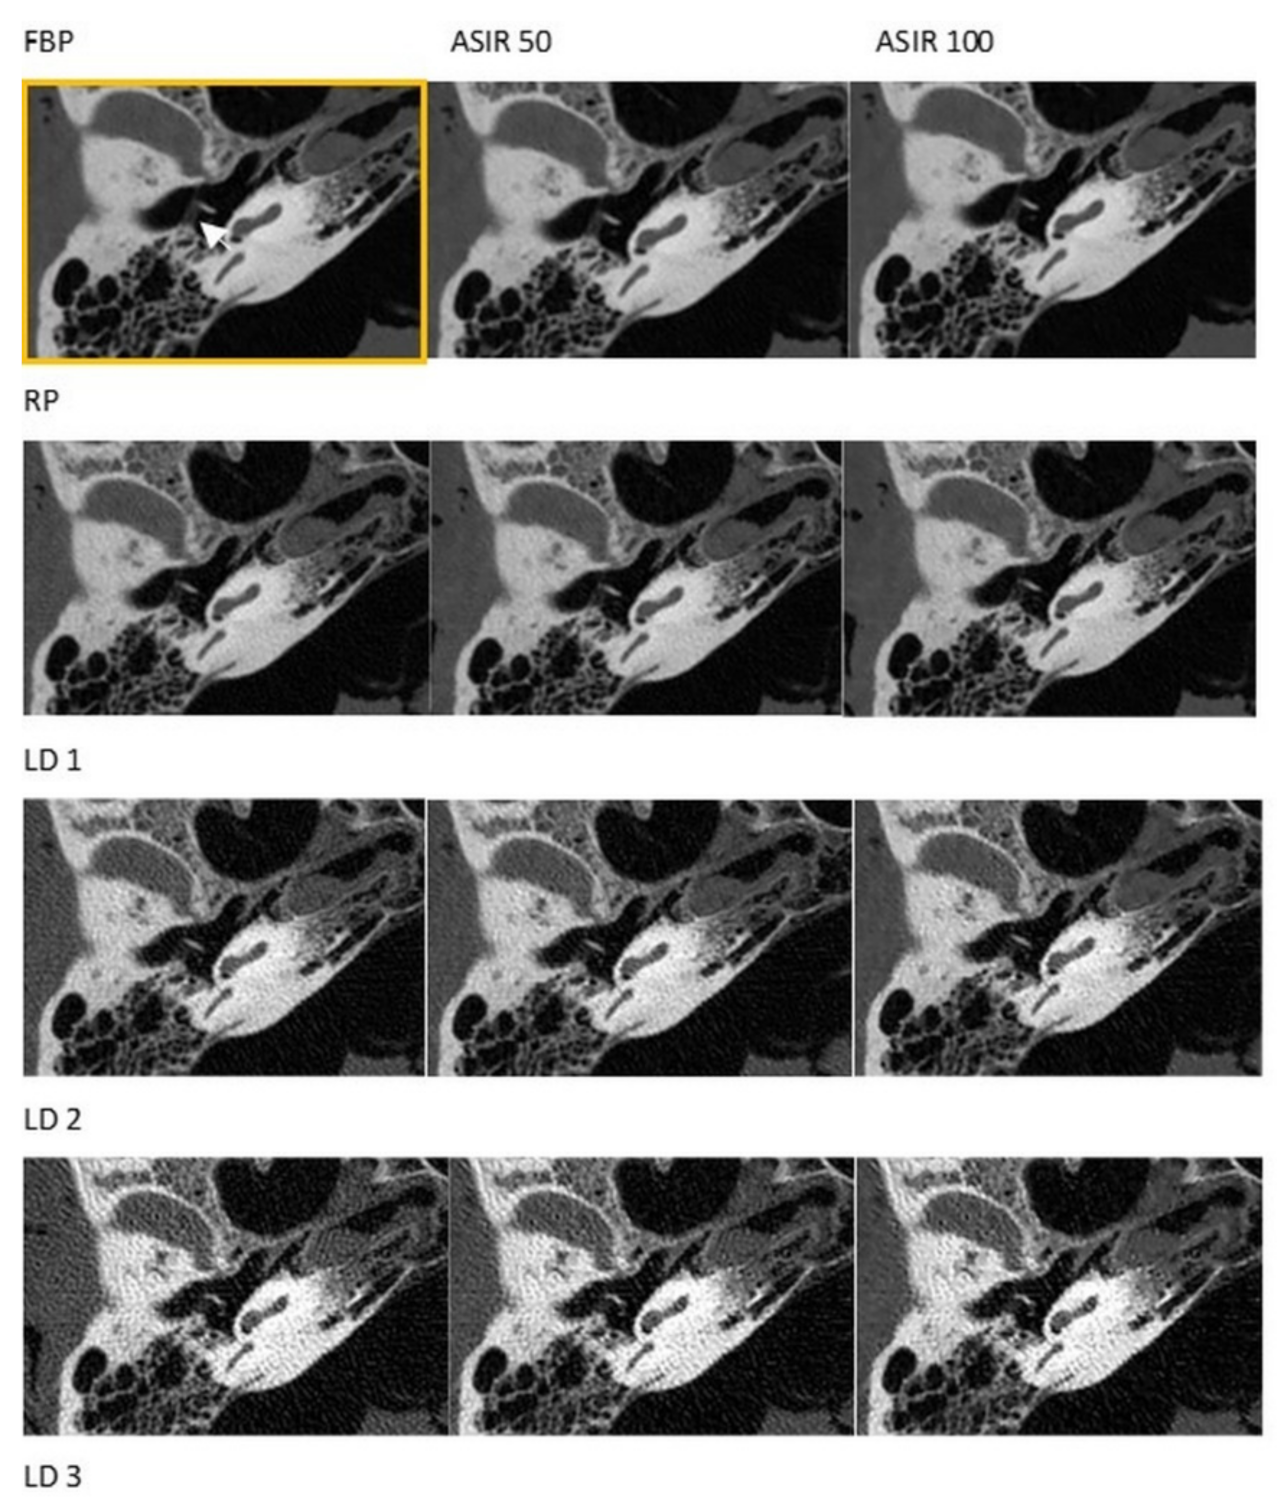

3.1. CT

3.2. CBCT